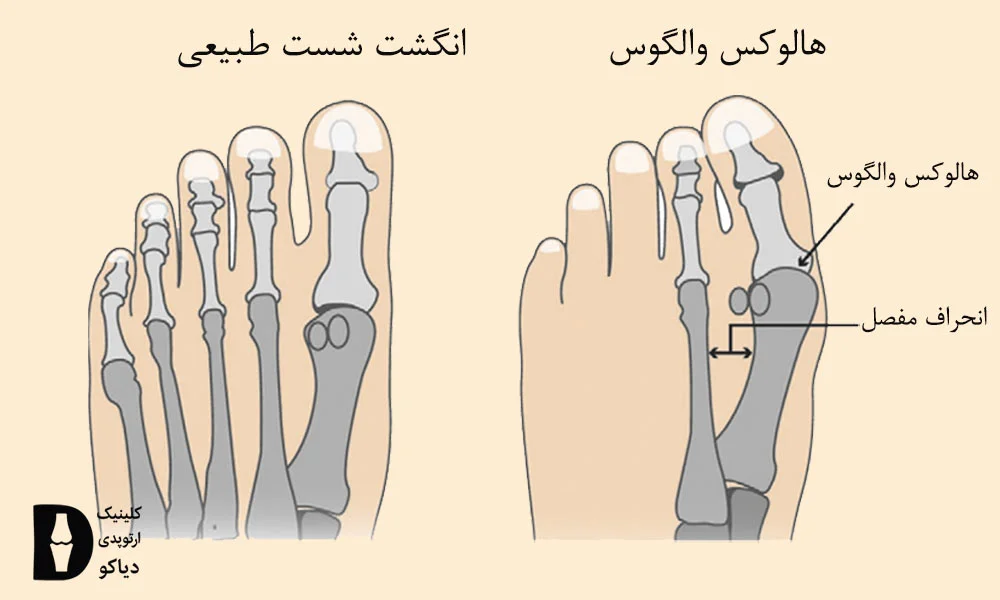

هالوکس والگوس یا انحراف شست پا چیست؟

هالوکس والگوس یا انحراف شست پا، یک مشکل شایع در پا است که در آن شست بهتدریج به سمت انگشت دوم متمایل میشود. این انحراف باعث میشود یک برآمدگی استخوانی در کنار مفصل شست به وجود بیاید که به آن «بونیون» میگویند. این برآمدگی میتواند دردناک باشد، باعث تورم شود و پوشیدن کفش را دشوار کند.

دلایل مختلفی در شکلگیری این عارضه نقش دارند که از جمله آنها میتوان زمینه ژنتیکی، پوشیدن کفشهای نامناسب (مثل کفشهای نوکتیز یا پاشنهبلند)، فشار زیاد به پاها و اضافهوزن را نام برد.

منابع علمی هالوکس والگوس را با استفاده از تصویر رادیوگرافی و بر اساس زاویه انحراف انگشت شست به 3 درجه خفیف، متوسط و شدید تقسیم میکنند.